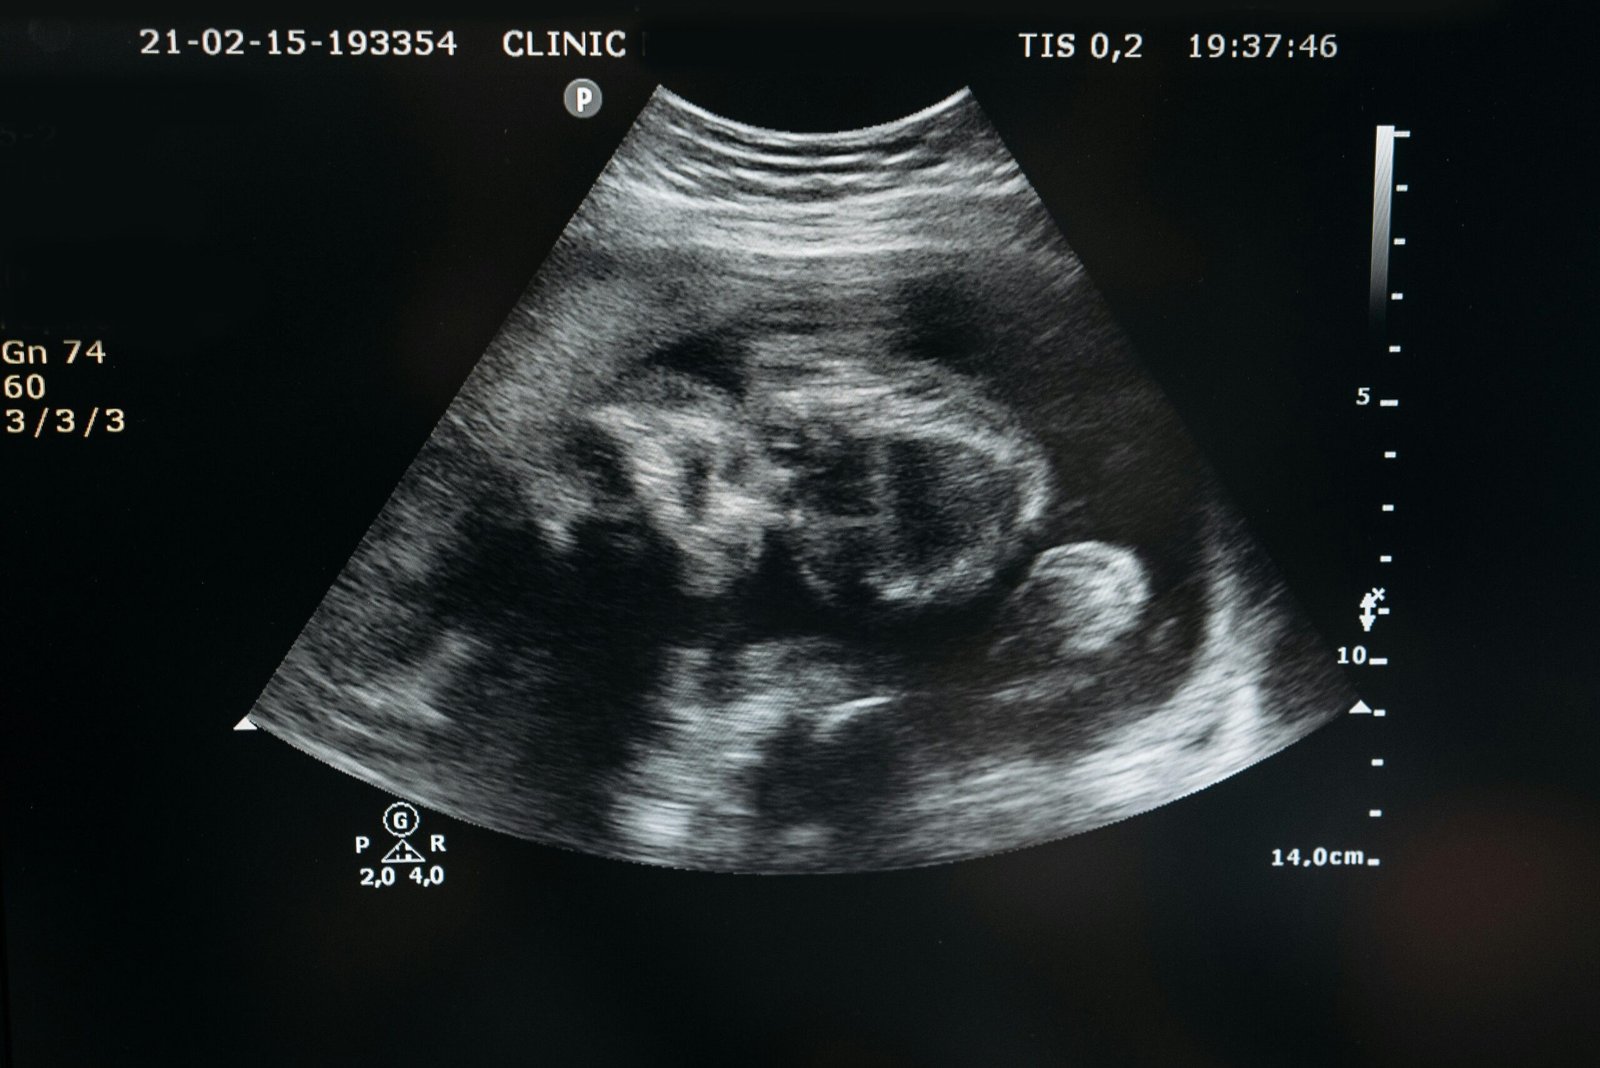

• الحمل ومتابعته (وفق طلب الطبيب)

• متابعة الحمل (بحسب البروتوكول الطبي)